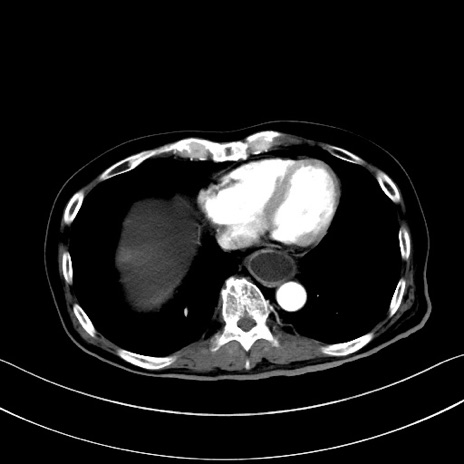

症例28(横断像)

【症例】60歳代男性

【主訴】嘔吐

【現病歴】胃癌にて胃全摘後。食思不振が悪化し、夜中に嘔吐することがある。

【既往歴】胃癌、胃全摘、脾摘、胆摘後

【データ】WBC 5900、CRP 10.56